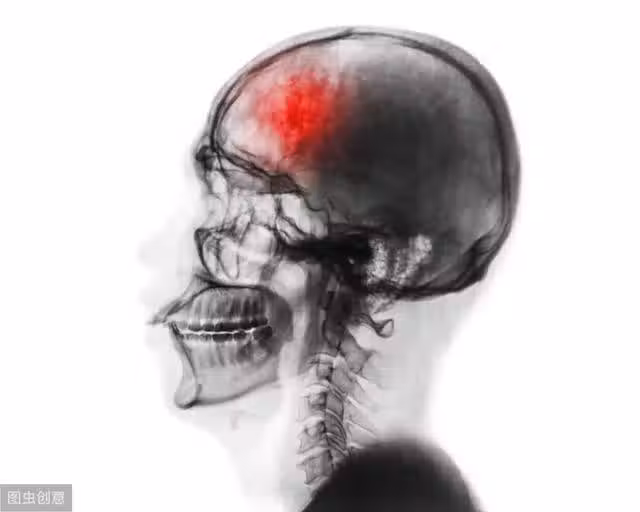

腦中風的5大徵兆不可輕忽

以上說的這兩種輕微中風,雖然症狀很快就會消失,但卻是未來可能發生更嚴重腦中風的先兆,醫生預估再次發生中風的幾率一般人的4到5倍,所以必須嚴加註意。

有關部門的一項調查結果顯示,65歲以上的國人有11.6%疑似發生過小中風,40到64歲人也有3.41%疑似發生過小中風,但竟然有37%的人沒有做進一步的檢查

近70%的人沒有做體重控制,顯示人們不重視小中風的威脅。